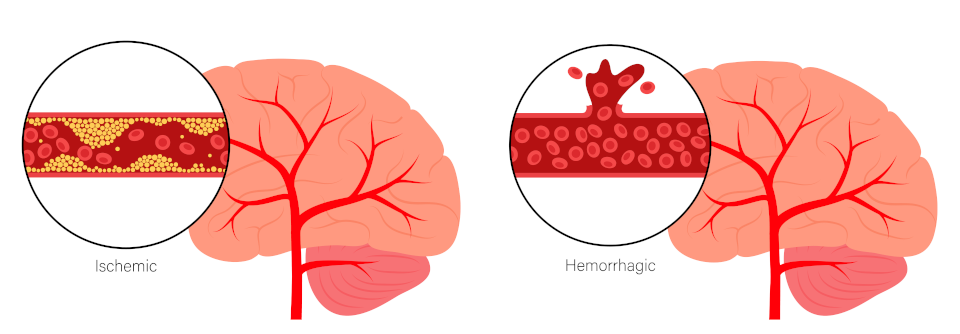

Für die Sekundärprävention steht nach einem ersten hämor­rhagischen Schlaganfall die Blutdrucksenkung im Fokus. Nach einer Ischämie sind die antithrombotische Therapie, eine Kontrolle der Risikofaktoren für Arteriosklerose und ggf. eine Operation an den Karotiden am wichtigsten.

Eine antihypertensive Therapie mit einem Ziel von < 130 bis 139 mmHg (je nach Art des Infarkts) schützt auch Ältere deutlich, insbesondere vor intrakraniellen Blutungen. Außerdem wird eine Statintherapie in der Sekundärprävention empfohlen. Allerdings sind bei älteren Patientinnen und Patienten die LDL-Zielwerte nicht einheitlich festgelegt und die mögliche Beeinträchtigung der Muskelfunktion mit Sturzgefahr ist individuell zu berücksichtigen. Das Sturzrisiko ist auch bei Gabe der bei Vorhofflimmern grundsätzlich empfohlenen oralen Antikoagulanzien zu ­beachten.

Thrombozytenfunktionshemmer sind bei allen nicht-kardioembolischen und atherosklerotisch bedingten Schlaganfällen indiziert. Die Therapie sollte möglichst früh nach dem Schlaganfall beginnen. Für Glukosezielwerte nach stattgehabtem Schlaganfall liegen für die ältere Population nur wenige Daten vor: Für ansonsten fitte ältere Personen mit Diabetes wird ein HbA1c-Wert von ≤ 7,5 % angestrebt, während bei Gebrechlichkeit zur Vermeidung von Hypoglykämien ein Zielwert von bis zu < 8,5 % gilt.